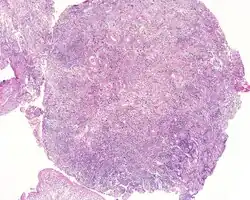

| An intermediate magnification of a H&E stained biopsy from an otic polyp. | |

By microscopic exam, the polypoid appearance is maintained, showing a granulation-type tissue reaction with edematous stroma and a rich investment by capillaries. The surface of the polyp is covered by stratified squamous epithelium with a prominent granular cell layer. The tissue is filled with lymphocytes, plasma cells, mast cells, histiocytes, and eosinophils. It is not uncommon to see plasma cells with Russell bodies and Mott cell formation. Depending on length of symptoms, multinucleated giant cells and calcifications may be seen. Other disorders may be concurrently present, especially since this is a post infectious/inflammatory disorder, and these include a cholesterol granuloma, "tunnel clusters" (glandular epithelial inclusions below the surface epithelium), and cholesteatoma.[3][4][5]